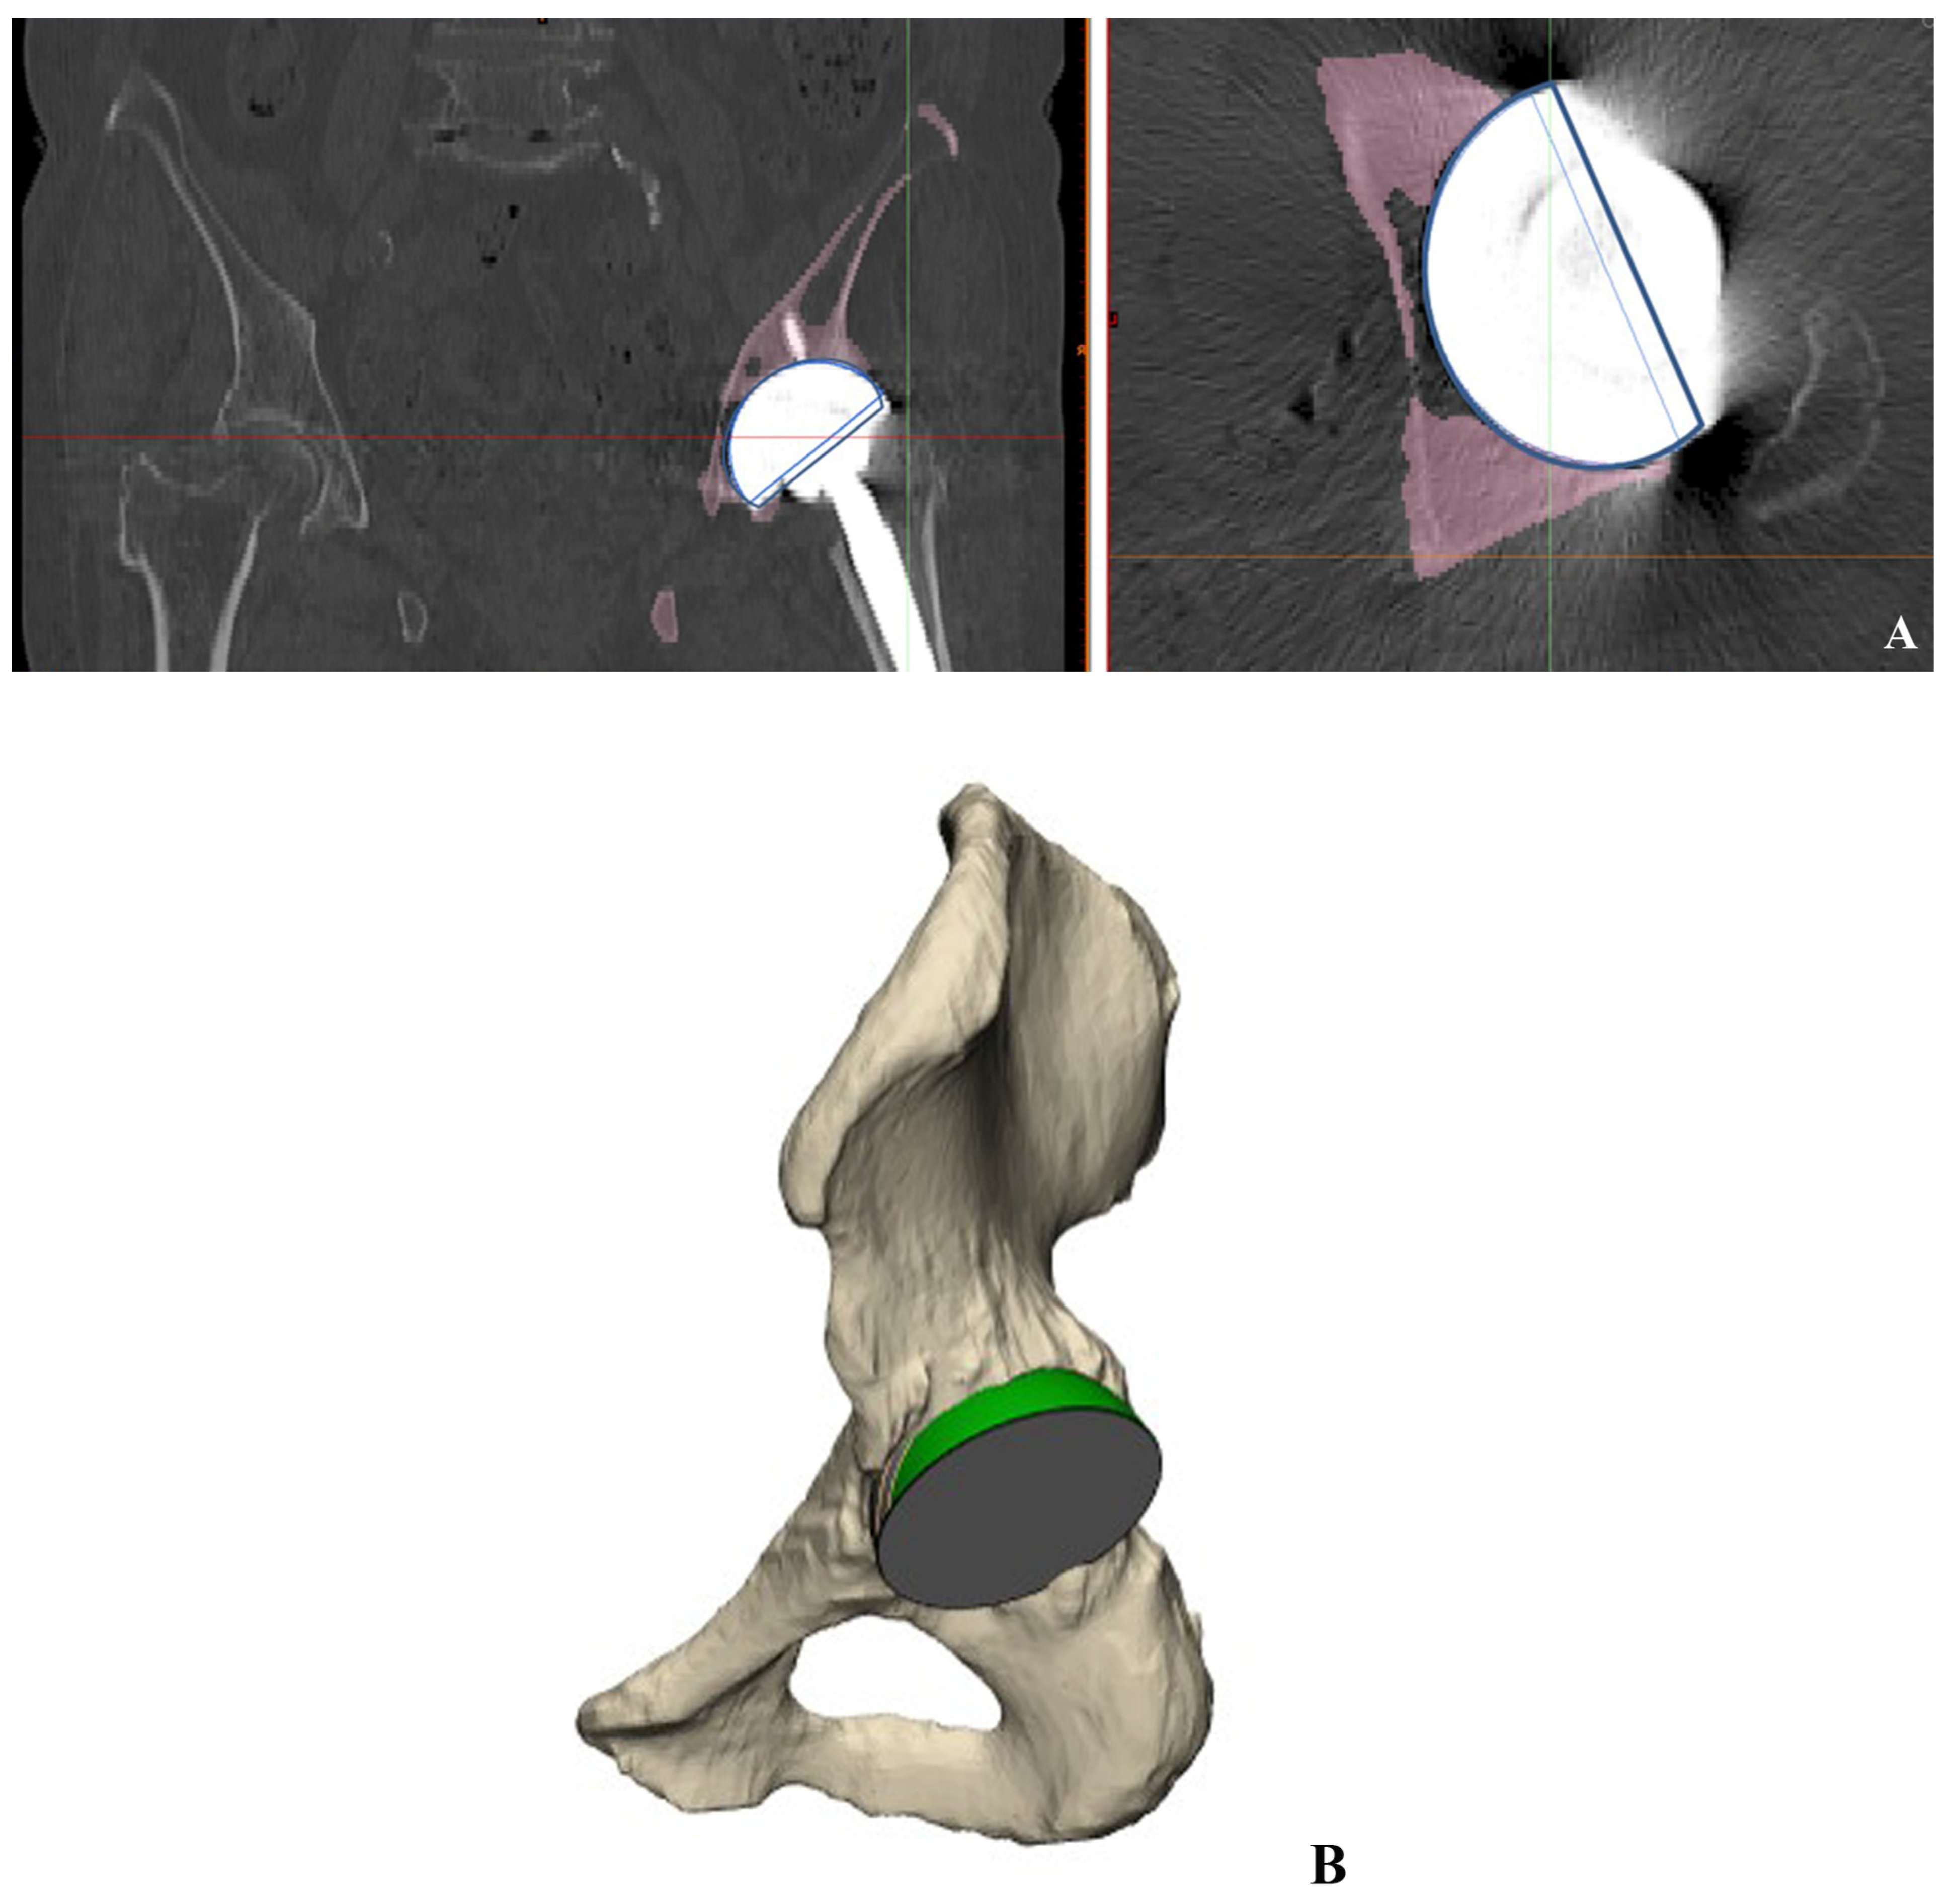

2.4. Cup Position and Fixation

2.6. 3D-Based Measurement of Host Bone Coverage from CT Scans

2.7. Measurement of Intra-Operative Host Bone Coverage